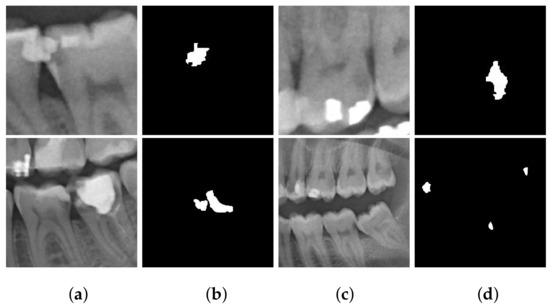

In the second step, the ground truth of the labeled dataset was generated using the ImageJ tool. Figure 3 displays some sample ground truth images generated from the panoramic X-ray images with cavities.

Figure 3. Sample panoramic X-ray images from Ivisionlab [41] associated with their ground truth. (a,c) Annotated images; pink indicates the location of the cavity on the panoramic X-ray image. (b,d) The ground truth that will be used as the ground truth for the model train. The white region indicates the segmented cavity.

The new ground truth had a large space of black color as a background and a small spot of white color corresponding to the cavity. This imbalance problem affected the performance in the cavity detection task since a large area of each image was the background. To improve the results, the images were cropped to reduce the unnecessary background and balance the classes in the ground truth. Figure 4 presents some samples of the images and ground truth after the cropping process. The number of images in the cropped dataset was 673 with dimensions of 512 × 512 pixels.

Figure 4. The samples of cropped images: (a,c) original cropped image and (b,d) ground truth.